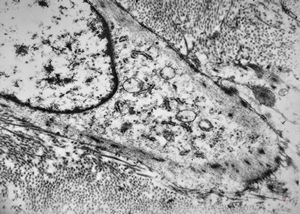

M,3m. | type II. pneumocyte

M,3m. | surfactant